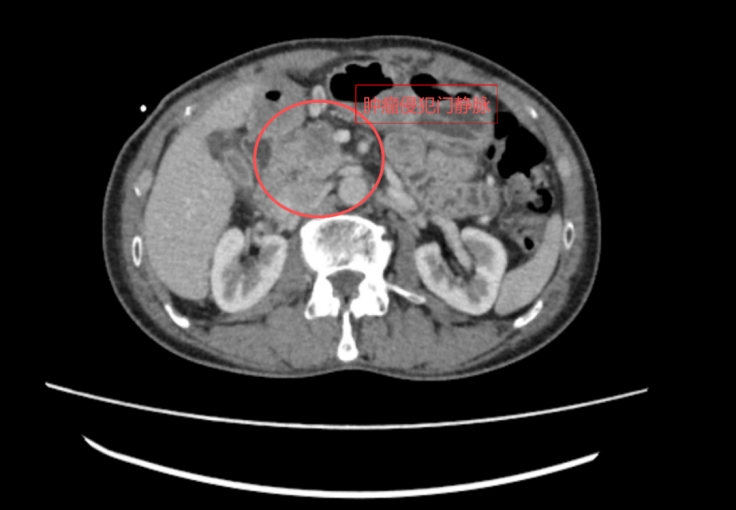

朱先生(化名)10天前突然出现身黄、目黄,小便颜色如浓茶样,前往广医五院肝胆胰外科就诊做腹部增强CT发现胰腺占位,考虑胰腺癌,肿瘤位于胰腺头部,周围环绕胆管、胃、十二指肠等重要器官,且肿瘤已累及门静脉主干,消化器官回流至肝脏的血管在此交汇,位置刁钻,手术难度极大,稍有不慎便可能引发致命性出血,风险极高。

患者术前CT(红圈内为肿瘤病灶)